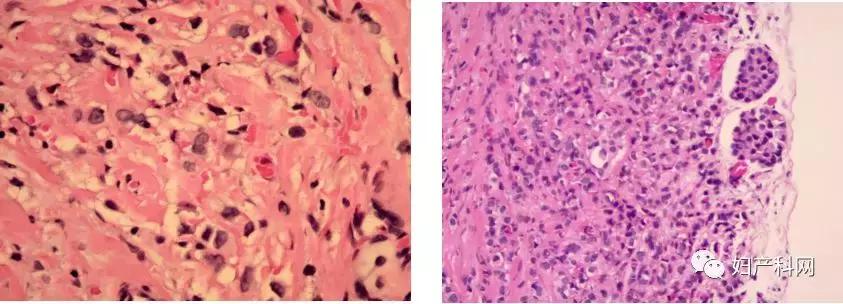

考虑患者目前一般情况可,盆腔包块较前明显增大,且伴有腹腔积液,如继续期待观察存在病灶扩散,出现恶液质,无法耐受手术可能,故讨论后于2019-4-3在全麻+硬膜外麻醉下行剖腹探查术,术中见:腹腔内见约200ml血性腹水,部分肠管致密粘连左侧盆壁。子宫萎缩,子宫前壁及其下段与腹壁广泛致密粘连,表面未见肌瘤样结节凸起。右侧卵巢呈囊实性增大,大小约6.0*5.0*6.0cm,表面不规则结节样凸起,呈多房,部分囊性,与周围组织无粘连;左侧卵巢呈囊实性增大,大小约4.0*4.0*3.0cm,表面不规则结节样凸起,呈多房,部分囊性,与周围组织无粘连。双侧输卵管匍匐在其同侧卵巢上,质地僵硬,未见明显积水增粗,伞端可见。子宫直肠陷凹存在。结合术前谈话,遂行双侧附件切除术。术中快速病理结果为:(双侧)卵巢癌,首先考虑转移性。结合术前谈话及术中病理提示,目*考前**虑转移性卵巢癌,遂行全子宫切除。术中探查大网膜、盆腹腔腹膜、肠管表面、阑尾及肝脏、脾脏、胃及膈顶等盆腹腔脏器表面未见明显病灶。术中一侧附件及标本剖解图(见图3)。

图3

术后常规病理报告提示(见图4):(双侧)卵巢、输卵管、卵巢血管区转移性癌,符合转移性乳腺癌所见。(腹腔积液)涂片内找见癌细胞。子宫浆膜表面见转移性癌,符合转移性卵巢癌所见。

结合患者术中及术后病理结果,术后转移性卵巢癌诊断明确。